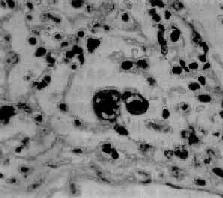

图9-21 腺病毒肺炎

图中央可见肿大肺泡上皮细胞中的核内包含体